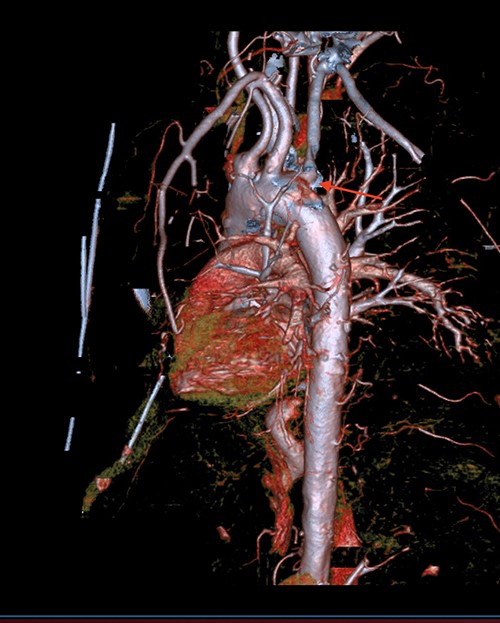

A 71-year-old male with past medical history of type 2 diabetes and hypertension presented to the emergency department at St. Joseph’s University Medical Center with severe respiratory distress. On nonrebreather, the patient’s oxygen saturation was 49%. The patient was subsequently intubated. Evaluation revealed pneumonia secondary to COVID-19 leading patient to be intubated on ventilator support for 4 weeks. During this time patient was maintained on enteral feeding through nasogastric tube, and was on gastrointestinal prophylaxis Protonix 40 mg daily for the duration of his admission. Ultimately, the patient made full recovery and was sent home; however, approximately 3 weeks later, he presented to the emergency department due to syncope. The patient experienced large-volume bright red hematemesis. He became hypotensive and was transfused three units of packed red blood cells and started on pressors. The patient was intubated and transferred to the intensive care unit (ICU) with acute blood loss anemia and hypovolemic shock. Here, an esophagogastroduodenoscopy (EGD) was performed revealing midesophageal bleed (Fig. 1). Hemostasis was achieved with clipping; however, post-procedurally, the patient again became hypotensive. Repeat EGD showed a nonbleeding esophageal ulcer with three clips in good position (Fig. 2). Computed tomography (CT) angiogram of the thorax was performed revealing an actively bleeding aberrant right subclavian artery perforating into the esophagus (Figs 3 and 4). The right subclavian artery was noted to be of normal caliber without ectasia or aneurism and the esophagus was free of any other pathology. Thoracic and vascular surgery were consulted; however, the bleed was deemed of nonsurvivable pathology due to comorbidities and current clinical status. Ultimately, the family of the patient decided to withdraw care and the patient passed.

CT thoracic angiogram showing actively bleeding aberrant right subclavian artery perforating into the esophagus (red arrow).

CT thoracic showing the arch of the aorta with the take-off of the right subclavian artery (red arrow) distal to the left subclavian artery.